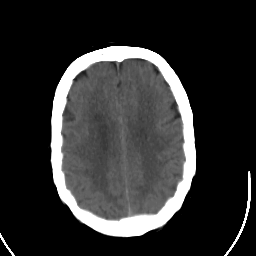

Stroke CT #2 -- Slice #18

[Home][Help][Clinical] Slice 18